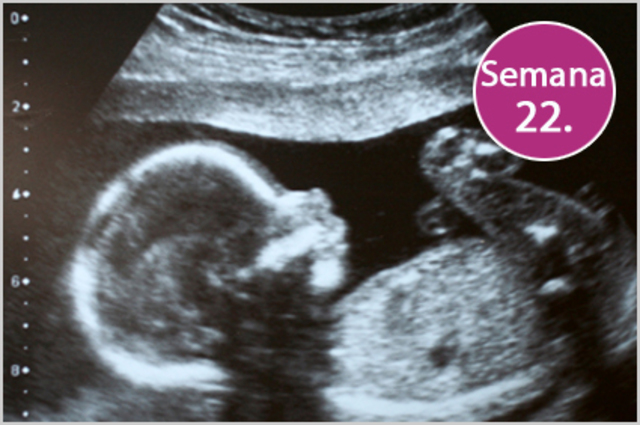

• Semana 21 a la 25

Semana 21 a la 25

Su cuerpo continua cubierto de lamugo y su piel está arrugada. Ya tiene pestaas y aunque sus ojos siguen cerrados, el iris va adquiriendo el color. Empieza a tener un esbozo de dientes. Los pulpones tienen la capacidad de expandirse, por lo que el feto podría respirar fuera del útero, en caso de nacimiento prematuro.